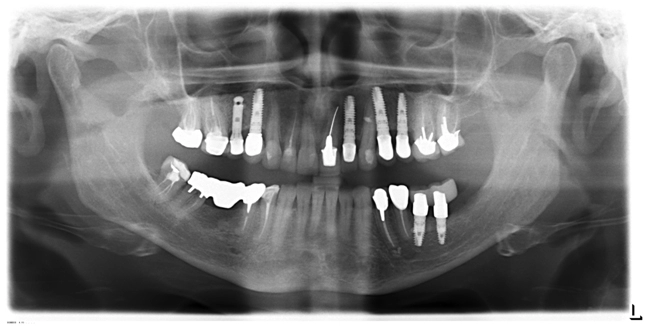

Пациентка Ш., 64 года

Жалобы на подвижность искусственной коронки, установленной около 10 лет назад в другом ЛПУ.

Объективно:

·         клиническое и рентгенологическое обследования показали, что прогноз повторного эндодонтического лечения неблагоприятный, корень восстановлению не подлежит;

·         имеются идеальные показания (отсутствие воспаления в области предполагаемого имплантата) для одномоментного удаления зуба 2.1, имплантации и немедленной нагрузки.

Контрольный постоперационный снимок показал удовлетворительное соединение имплантата с костной тканью лунки.

·         Зубы2Первый осмотр – через 1 неделю после операции.

·         Повторные осмотры – через 1 месяц после операции, через 3 месяца.

·         Смена временной конструкции через 6 мес.

·         Постоперационное течение без особенностей.

Через 2 года.

Клинически и рентгенологически имплантат остается стабильным. Ортопедическая реставрация состоятельной.